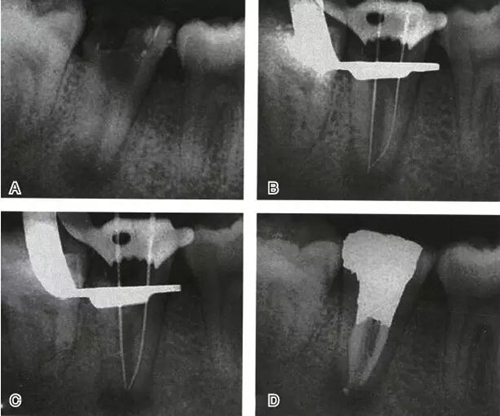

C形根管系統(tǒng)的近舌及遠(yuǎn)中根管仍可按常規(guī)方法作根管治療,但慎用G鉆。經(jīng)K3銼預(yù)備后有一定效果(圖3),但單純機(jī)械預(yù)備很難達(dá)到預(yù)期效果,應(yīng)輔以化學(xué)預(yù)備。在橡皮障隔濕條件下,采用5.25%次氯酸鈉結(jié)合超聲沖洗是徹底清理狹區(qū)的關(guān)鍵。不能使用橡皮障時(shí)可使用1%次氯酸鈉溶液反復(fù)多次沖洗,亦有顯著效果。手術(shù)顯微鏡及根管內(nèi)窺鏡的使用有助于提高根管預(yù)備的質(zhì)量。

圖3 K3銼預(yù)備C形根管,A:預(yù)備前,B:預(yù)備后

根管充填是C形根管治療成功與否的最重要因素。充填C形根管系統(tǒng)時(shí),近舌及遠(yuǎn)中根管可以進(jìn)行常規(guī)充填。關(guān)于狹區(qū)的充填,更適合以熱牙膠垂直加壓充填,這種方法可使牙膠到達(dá)根管系統(tǒng)的每一死角(圖4~7)。

圖4 Ⅰ型C形根管治療典型病例一,A:初始片,B:初尖銼片,C:主尖銼片,D:充填片